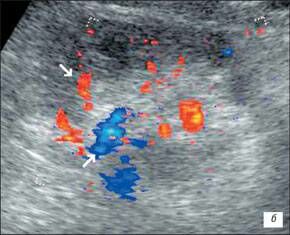

Доплерограма

На малюнку помітно зниження функції нирок виявляється ненасичений інтраренального малюнка, зниження по часу або мінімальної швидкості кровотоку. Всі ці критерії характеризуються патологією і потребують оперативного втручання.

Сканування лівого сечівника через сечовий міхур. На доплерограмах чітко видно криву ретроградногопотіку сечі. Швидкість потіку 0,52m/s, Час 1,16s)

Сканування лівого сечівника через сечовий міхур. На доплерограмах чітко видно криву ретроградногопотіку сечі. Швидкість потіку 0,22m/s, Час 2,38s)

На доплерограмі сечоводів СМР 2,3 і4 ступені спостерігається: делятація сечівника в нижніх і верхніх відділах при середньому або максимальному наповнені сечового міхура, циклічні зиіни діаметра сечівника в нижніх і верхніх відділах: доплерографічна регістрація зворотнього току сечі в сечоводі:стабільне розширення миски: зменшення розмірів нирки.